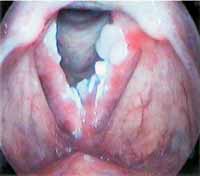

A papilomatose laríngea, uma condição que afeta as cordas vocais, exige atenção especial em diversos aspectos da vida, e a alimentação é um deles. Compreender como certos alimentos podem impactar a laringe e o sistema imunológico é crucial para quem convive com essa questão. O foco principal é fortalecer as defesas do corpo e minimizar os fatores que podem agravar a inflamação local.

O vírus do papiloma humano (HPV) é o principal causador da papilomatose laríngea. Por isso, fortalecer a imunidade é um passo fundamental. Isso significa oferecer ao corpo os nutrientes necessários para que ele possa combater o vírus de forma mais eficaz. Uma resposta imune robusta pode ajudar a controlar a replicação viral e a reduzir a frequência ou gravidade das lesões.

O refluxo laringofaríngeo, muitas vezes chamado de “refluxo silencioso”, é um fator que pode agravar a papilomatose laríngea. Quando o conteúdo ácido do estômago retorna até a região da laringe, ele causa irritação e inflamação. Essa inflamação pode criar um ambiente ainda mais propício para o desenvolvimento ou piora das lesões causadas pelo papiloma.